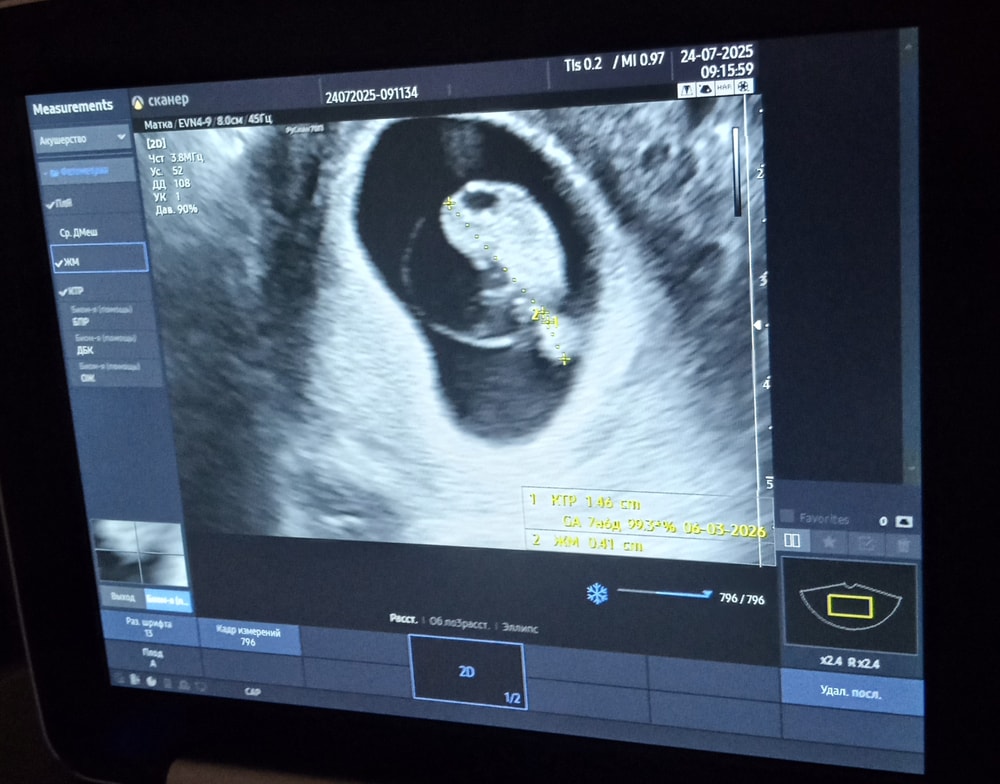

Моя беременностьСегодня срок 7.4

Отслойка уменьшилась с 13 мм до 3.5 мм славо богу.

Мое узи, мой маленький малыш, мой ребенок . Все кажеться что будто это все не со мной происходит . Чудо .

Сегодня срок 7.4